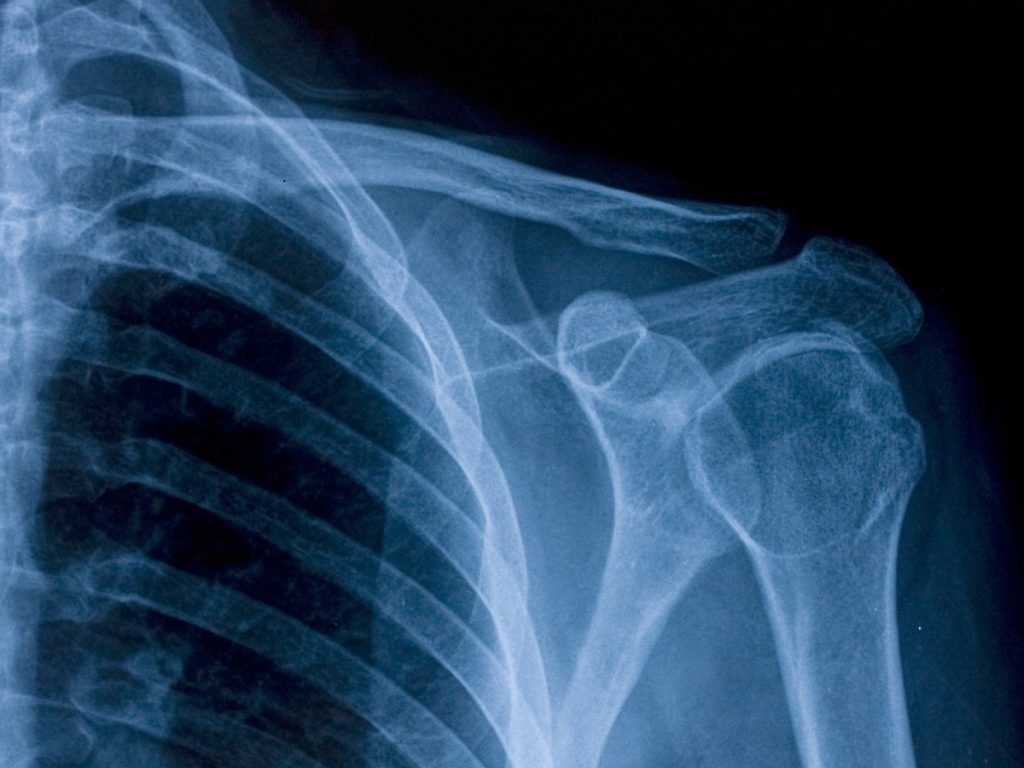

Your shoulder is one of the most flexible and hardworking joints in your body.

It’s designed to lift, twist, and reach in nearly every direction. But that flexibility also makes it prone to strain, wear, and injury.

The bones, tendons, ligaments, and cartilage work together to help your shoulder move smoothly. When even one of them is irritated or damaged, it can cause pain and stiffness.

If needed, Dr. Mehta may recommend targeted imaging, such as X-rays, ultrasound, or MRI, to pinpoint the source of your shoulder pain.